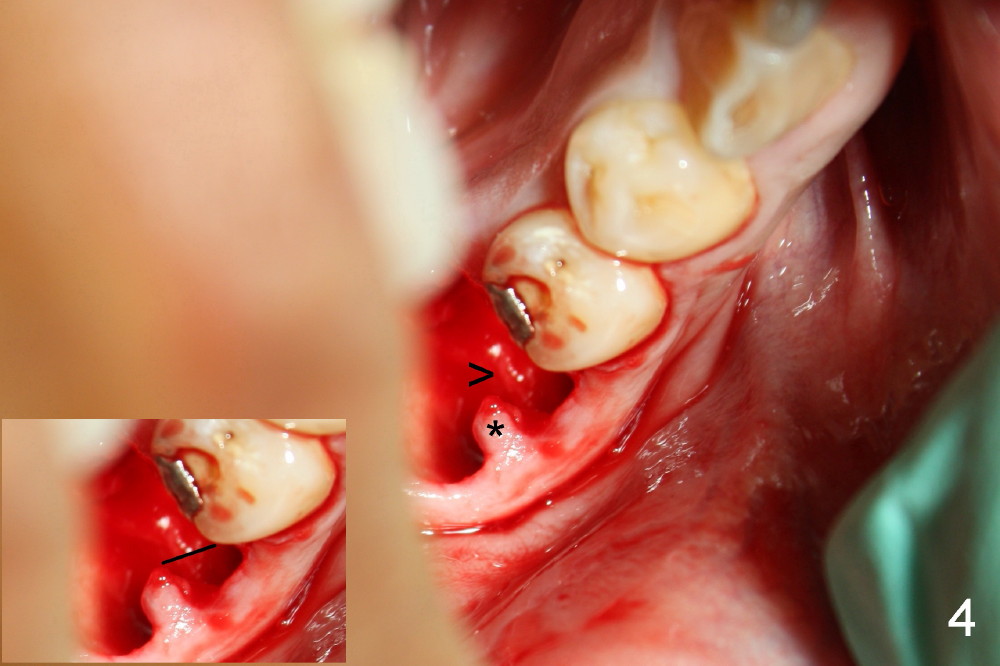

A 38-year-old lady agrees to have implant placement 7 years after loss of the crown of the lower right first molar (Fig.1,2). When the tooth is extracted, the septum is found to be low (Fig.3,4). To confirm it, a PA is taken (Fig.5). To initiate an osteotomy in the septum, it is trans-sectioned with thin osteotomes as shown in Fig.4 insert (black line). A 2 mm pilot drill is placed in the septum (Fig.6: P). The osteotomy is enlarged by 2.5-4.0 mm reamers (Fig.7,8), followed by insertion of 6x17 mm tapered tap at the depth 14 mm (Fig.9). The osteotomy is further enlarged by 4.5 and 5.0 mm reamers. A 6.0x14 mm one piece implant is placed initially. The trajectory is not ideal. A 6.0x14 mm one piece implant is placed initially. The trajectory is not ideal. The implant is removed from the osteotomy partially and reinserted with improved trajectory (Fig.11, compare to Fig.10 (red line)). Primary stability is high. There is not much bone mesiodistally so that the trajectory is easily changed in that direction. After abutment preparation, mixture of autogenous bone (harvested from reamers) and allograft is placed in the residual mesial and distal sockets (Fig.12). To contain the bone graft, an immediate provisional is placed (Fig.13 P). The occlusal plane of the provisional is significantly lower than that of the adjacent teeth to avoid micromovement of the implant. The patient is advised to eat soft food on the left side. Six days postop, the patient returns for prophy. The provisional is removed; the bone graft appears to be incorporating into the socket (Fig.14). After recementation, the provisional remains in place for 3.5 months; PA shows increased bone density in the mesial and distal sockets (Fig.15, compare to Fig.5,11). Due to insurance coverage, the patient defers fabrication of definitive restoration for at least 7 months. The immediate provisional is finally lost 8.5 months postop: the gingiva attaches to the 1-piece implant (Fig.16), while the density of the mesial socket increases (Fig.17 *) with formation of the cortex (lamina dura) coronally (v). Before the provisional (Fig.18 P) is removed for cementation of the definitive restoration, black shadow (*) is noted over the buccal gingiva. It is partially due to buccal placement (Fig.19) and partially due to buccal atrophy over a period of 10.5 months postop. How to prevent buccal placement? Positioning the first pilot drill in the septum buccolingually is a key. Eleven months post crown (Fig.20 C) cementation, the black shadow remains, but there is no tenderness. If the implant threads are immediately underneath the periosteum, there is tenderness.